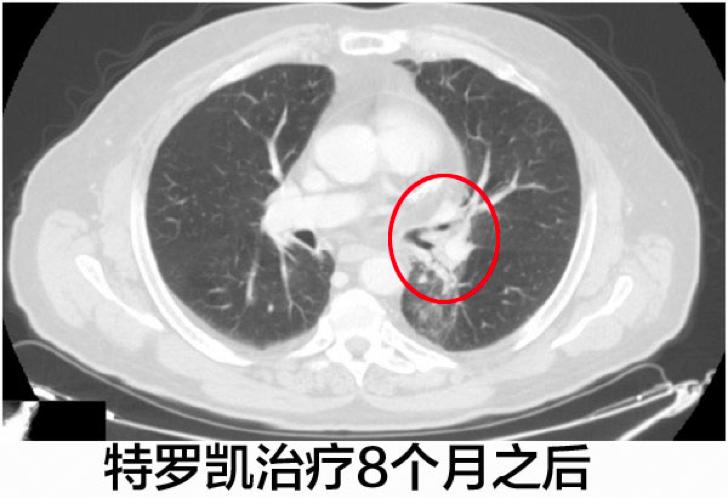

患者继续使用特罗凯进行治疗,四个月之后的CT影像学检查发现左肺下叶肿瘤显著缩小,至7毫米。